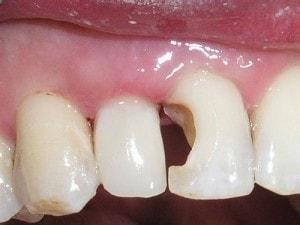

Composite buildup

Tooth #7 is vital

Crown would require root canal and post for retention. Unfortunately, there is no ferrule for a crown.

Pre-opt incisal view

PA #7